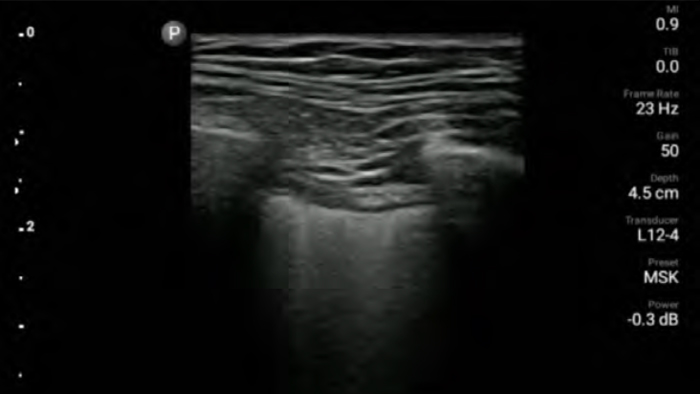

Lleve el ultrasonido a la cabecera del paciente

El uso de Lumify junto a la cama de sus pacientes puede ser una herramienta valiosa para determinar el estado del contenido estomacal y puede reducir el riesgo de aspiración pulmonar. En conjunto, esto puede reducir el riesgo de complicaciones por anestesia.